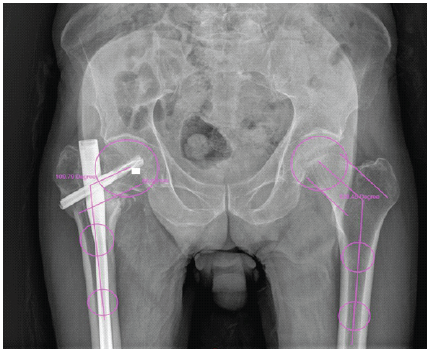

An 85-year-old man reported to the emergency room (ER) with pain, swelling, external rotation deformity of the right lower limb, and inability to walk as a result of a traffic collision (2-wheeler vs. pedestrian). In the ER, the ATLS protocol was followed. The patient was clinically and hemodynamically stable, and there were no systemic injuries on the primary survey. He was sent for a radiograph after stabilization, and it revealed a stable intertrochanteric fracture of the right femur (AO/OTA classification A 1.2), with a Singh’s Index of grade 3 (Fig. 1).

Figure 1: Pre-operative X-ray (AO/OTA A1.2).

Post-operative radiographs were obtained, and they showed a neutral reduction, a Baumgaertner’s Tip Apex Distance (TAD) of 19.73 mm, the neck shaft angle was 138°, and Parker’s ratio was 38.9% (Figs. 2 and 3).

Figure 2: Intraoperative assessment of tip apex distance (TAD) (a) in anterior posterior 9.09 mm, 10.64 mm in lateral view (b), and total TAD = 19.73 mm (c) neck shaft angle 138°s.

Figure 3: (a) Parker’s ratio 38.9%, (b) Cleveland zone-center/center

The post-operative fracture gap was <1 mm, and Garden alignment index was good, and the center of the helical blade was placed in the Cleveland zone center–center. The reduction quality was good according to the Baumgaertner reduction quality criteria, and excellent according to the Chang reduction quality criteria, respectively.